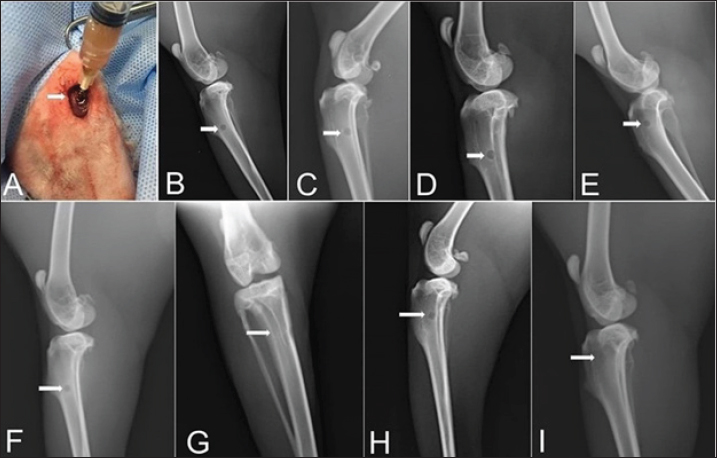

Zero-time radiographic evaluation following surgery demonstrated radiolucency; bone defect at the proximal part of the tibial tuberosity in all studied groups (Fig. 5). Whereas, postoperative follow-up radiographs (≤ 2 months) of the studied rabbits revealed a significant difference (p < 0.05) in bone regeneration between rabbits treated with Ag-NPs FG gel (group 2) at the fourth week and onward in comparison to the control group, and at the eighth week in comparison to rabbits treated with plain gel (group 3), and rabbits treated with FG gel (group 4) as depicted in (Fig. 5) and (Table 1).

Fig. 4. A) Viscosity profile of FG and AgNPs-FG loaded hydrogels at different shear rates; B) Rheograms of FG and AgNPs-FG loaded hydrogels at different shear stress values.Fig. 5. Skin incision at the medial aspect of the proximal end of the right tibia with the injection of AgNPs-FG-gel at the bone defect (A), immediate postoperative lateral radiographs of bone defect at tibia + normal saline control group (group1) (B), bone defect at tibia + AgNPs-FG (group 2) (C), bone defect at tibia + plain gel (group 3) (D), and bone defect at tibia + FG-gel (group 4) (E). Postoperative (day 56) lateral radiographs of bone defect at tibia + normal saline, (group1) (F), Cranio-caudal radiograph of bone defect at tibia + AgNPs-FG (group 2) (G), bone defect at tibia + plain gel (group 3) (H), and bone defect at tibia + FG-gel (group 4) (I). Please note complete healing in (G) compared to other studied groups.

Fig. 5. Skin incision at the medial aspect of the proximal end of the right tibia with the injection of AgNPs-FG-gel at the bone defect (A), immediate postoperative lateral radiographs of bone defect at tibia + normal saline control group (group1) (B), bone defect at tibia + AgNPs-FG (group 2) (C), bone defect at tibia + plain gel (group 3) (D), and bone defect at tibia + FG-gel (group 4) (E). Postoperative (day 56) lateral radiographs of bone defect at tibia + normal saline, (group1) (F), Cranio-caudal radiograph of bone defect at tibia + AgNPs-FG (group 2) (G), bone defect at tibia + plain gel (group 3) (H), and bone defect at tibia + FG-gel (group 4) (I). Please note complete healing in (G) compared to other studied groups.

Although the radiographic examination is the standard tool for the assessment and follow up of the healing process of various fractures, however, great efforts have been made in previous research toward developing new techniques for following the progress of bone fracture healing. Therefore, the collaboration between the radiographic, BTMs, and histopathological findings used in this study provides a promising tool for the subjective assessment of fracture repair. These results were inconsistent with El Shafaey et al. (2014), and Al-Sobayil et al. (2020). Postoperative radiographic follow-up (≤ 2 months) of the operated rabbits revealed a significant difference (p < 0.05) in bone regeneration between rabbits treated with Ag-NPs-FG gel (group 2) at the fourth week and onward compared to the control group and at the eighth week in comparison to rabbits treated with plain gel (group 3), and rabbits treated with FG-gel (group 4).